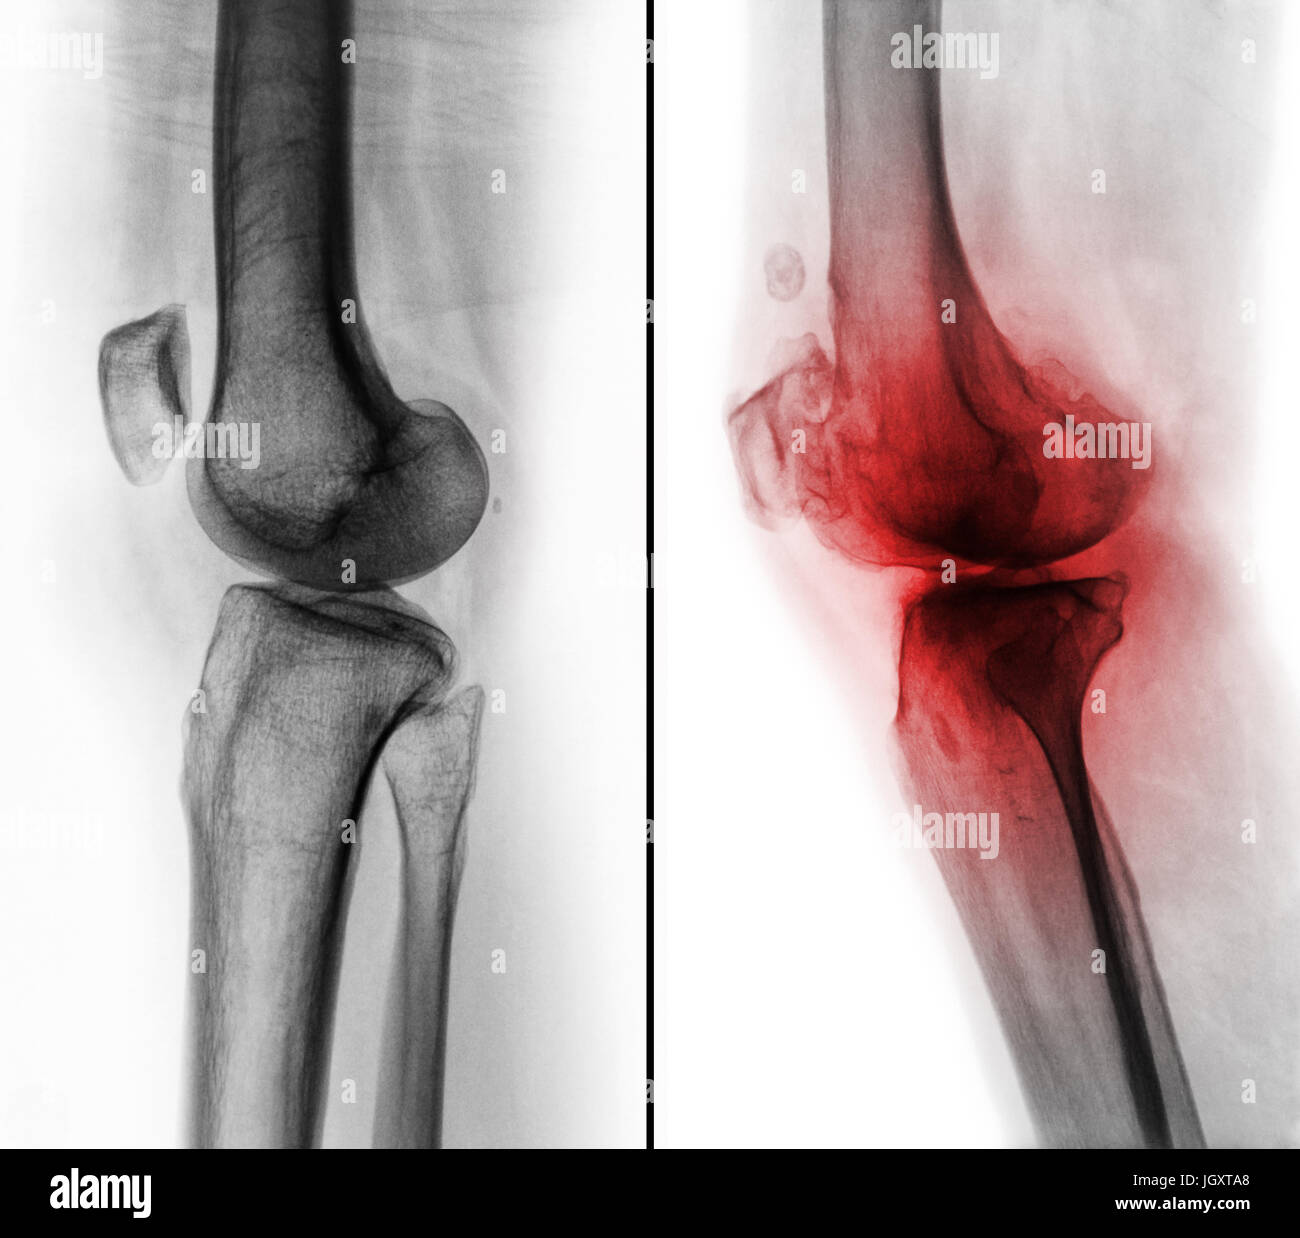

Comparaison entre le genou humain normal ( image de gauche ) et de l'arthrose du genou ( image de droite ) . Vue latérale . Banque D'Imageshttps://www.alamyimages.fr/image-license-details/?v=1https://www.alamyimages.fr/photo-image-comparaison-entre-le-genou-humain-normal-image-de-gauche-et-de-l-arthrose-du-genou-image-de-droite-vue-laterale-148107237.html

Comparaison entre le genou humain normal ( image de gauche ) et de l'arthrose du genou ( image de droite ) . Vue latérale . Banque D'Imageshttps://www.alamyimages.fr/image-license-details/?v=1https://www.alamyimages.fr/photo-image-comparaison-entre-le-genou-humain-normal-image-de-gauche-et-de-l-arthrose-du-genou-image-de-droite-vue-laterale-148107237.htmlRFJGXT85–Comparaison entre le genou humain normal ( image de gauche ) et de l'arthrose du genou ( image de droite ) . Vue latérale .

Comparaison entre le genou humain normal ( image de gauche ) et de l'arthrose du genou ( image de droite ) . Vue latérale . Banque D'Imageshttps://www.alamyimages.fr/image-license-details/?v=1https://www.alamyimages.fr/photo-image-comparaison-entre-le-genou-humain-normal-image-de-gauche-et-de-l-arthrose-du-genou-image-de-droite-vue-laterale-148107296.html

Comparaison entre le genou humain normal ( image de gauche ) et de l'arthrose du genou ( image de droite ) . Vue latérale . Banque D'Imageshttps://www.alamyimages.fr/image-license-details/?v=1https://www.alamyimages.fr/photo-image-comparaison-entre-le-genou-humain-normal-image-de-gauche-et-de-l-arthrose-du-genou-image-de-droite-vue-laterale-148107296.htmlRFJGXTA8–Comparaison entre le genou humain normal ( image de gauche ) et de l'arthrose du genou ( image de droite ) . Vue latérale .

Comparaison entre le genou humain normal ( image de gauche ) et de l'arthrose du genou ( image de droite ) . Vue latérale . Banque D'Imageshttps://www.alamyimages.fr/image-license-details/?v=1https://www.alamyimages.fr/photo-image-comparaison-entre-le-genou-humain-normal-image-de-gauche-et-de-l-arthrose-du-genou-image-de-droite-vue-laterale-148107261.html

Comparaison entre le genou humain normal ( image de gauche ) et de l'arthrose du genou ( image de droite ) . Vue latérale . Banque D'Imageshttps://www.alamyimages.fr/image-license-details/?v=1https://www.alamyimages.fr/photo-image-comparaison-entre-le-genou-humain-normal-image-de-gauche-et-de-l-arthrose-du-genou-image-de-droite-vue-laterale-148107261.htmlRFJGXT91–Comparaison entre le genou humain normal ( image de gauche ) et de l'arthrose du genou ( image de droite ) . Vue latérale .

Comparaison entre le genou humain normal ( image de gauche ) et de l'arthrose du genou ( image de droite ) . Vue latérale . Banque D'Imageshttps://www.alamyimages.fr/image-license-details/?v=1https://www.alamyimages.fr/photo-image-comparaison-entre-le-genou-humain-normal-image-de-gauche-et-de-l-arthrose-du-genou-image-de-droite-vue-laterale-148107279.html

Comparaison entre le genou humain normal ( image de gauche ) et de l'arthrose du genou ( image de droite ) . Vue latérale . Banque D'Imageshttps://www.alamyimages.fr/image-license-details/?v=1https://www.alamyimages.fr/photo-image-comparaison-entre-le-genou-humain-normal-image-de-gauche-et-de-l-arthrose-du-genou-image-de-droite-vue-laterale-148107279.htmlRFJGXT9K–Comparaison entre le genou humain normal ( image de gauche ) et de l'arthrose du genou ( image de droite ) . Vue latérale .